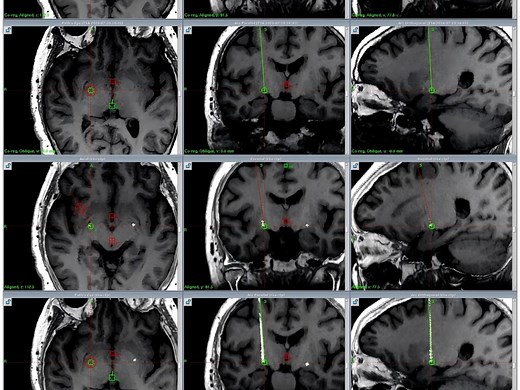

- DBS

Conversion Communications - Deep-Brain Stimulation

Parkinson Turkey - The Procedure of

DBS - DBS